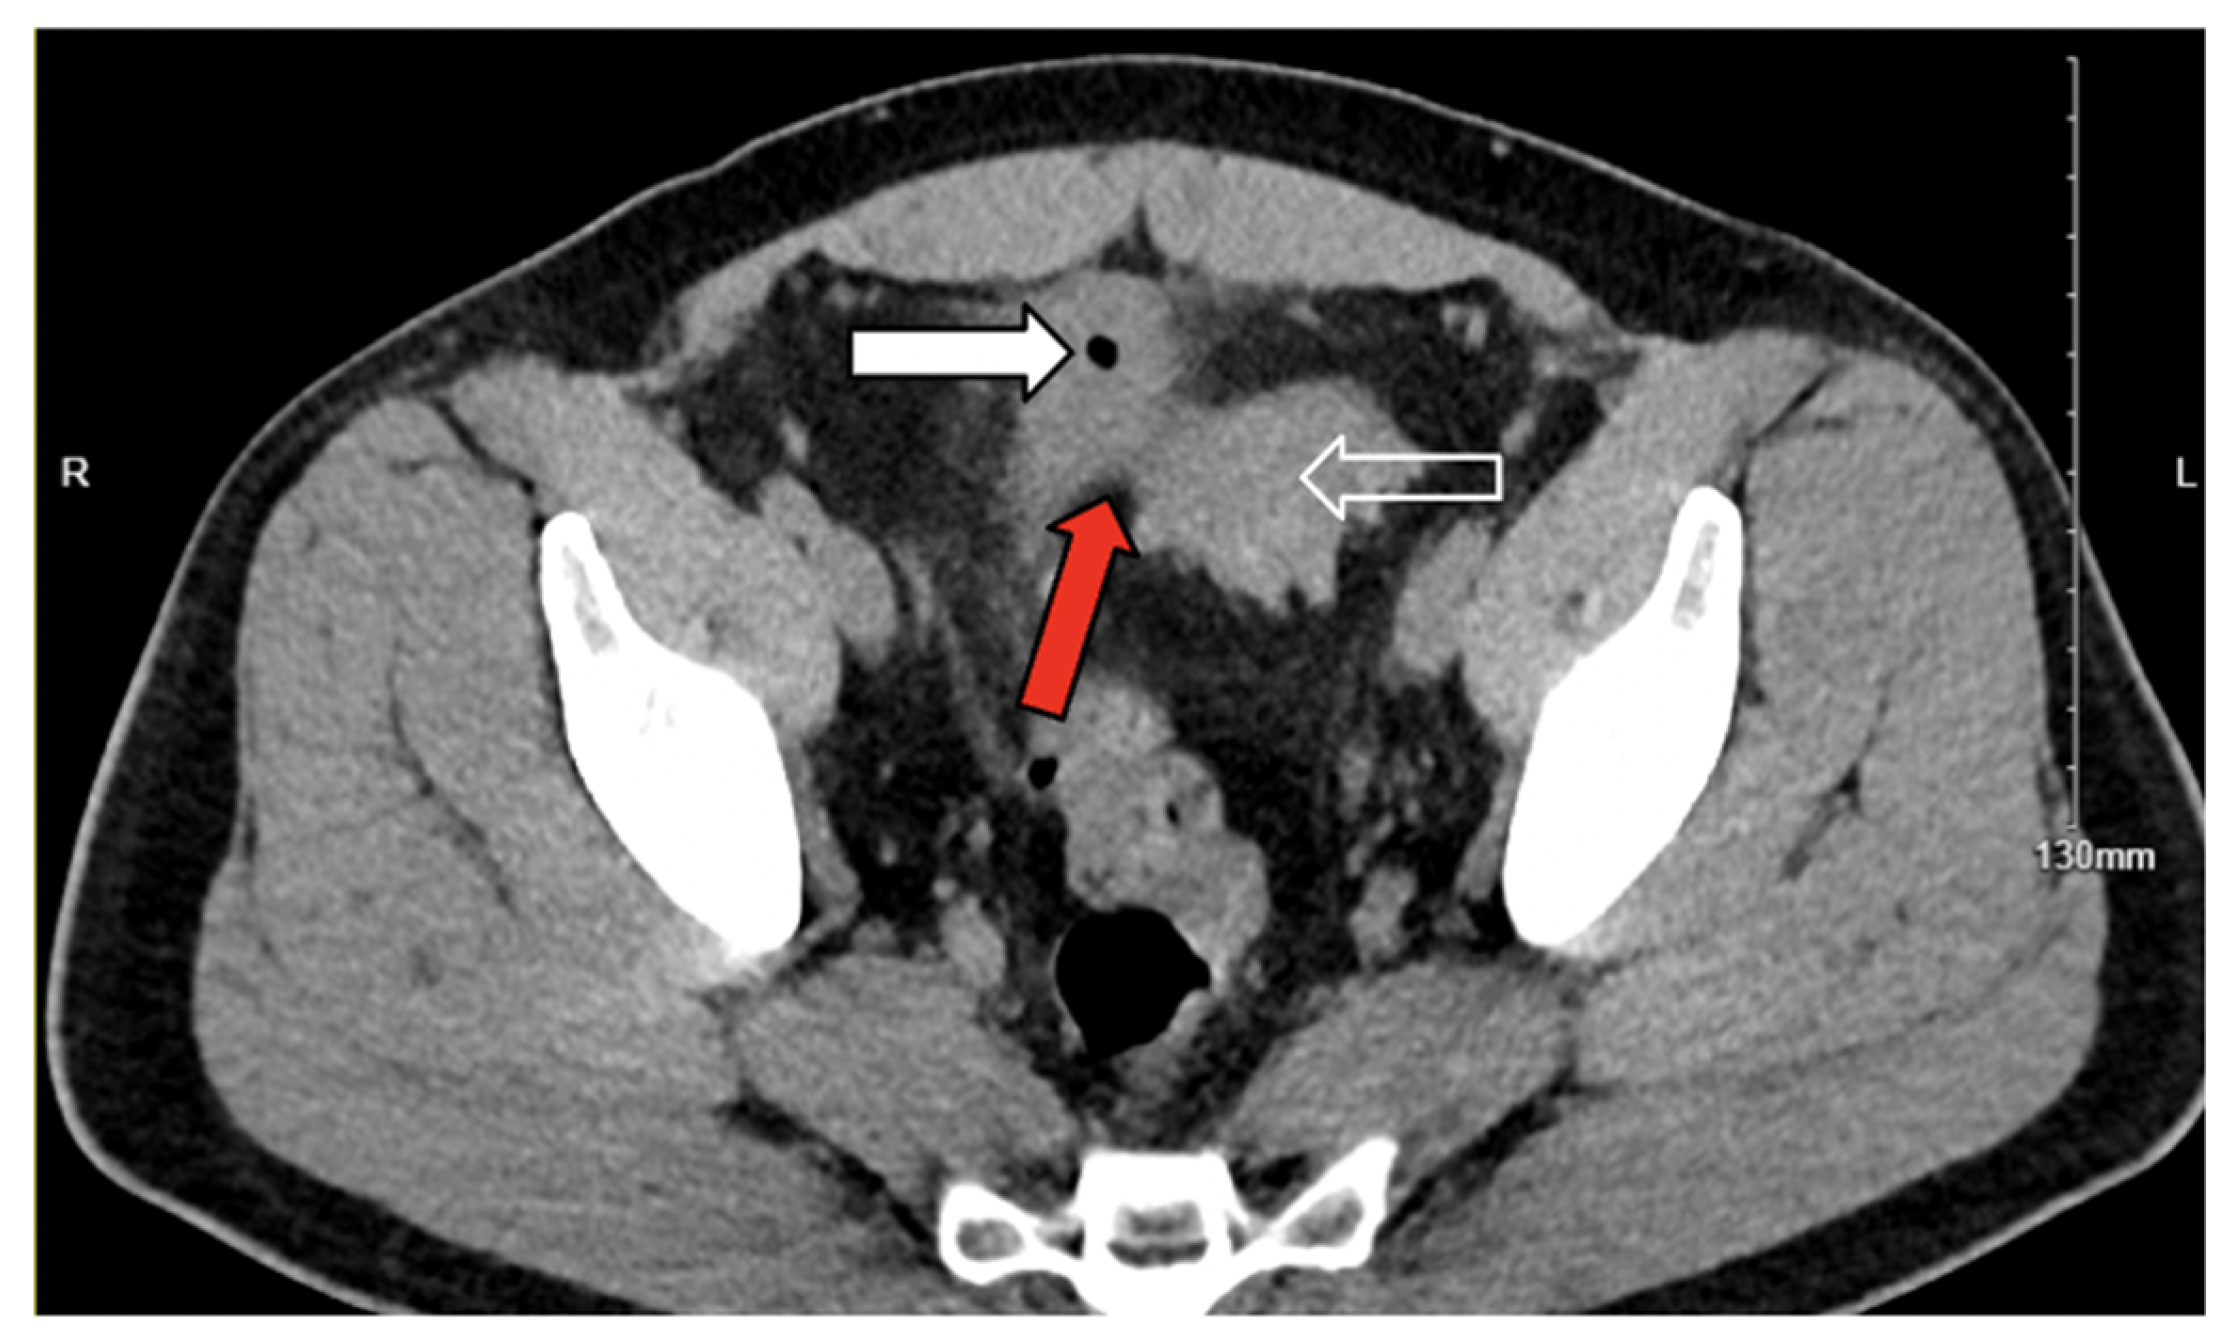

3.1. Case 1